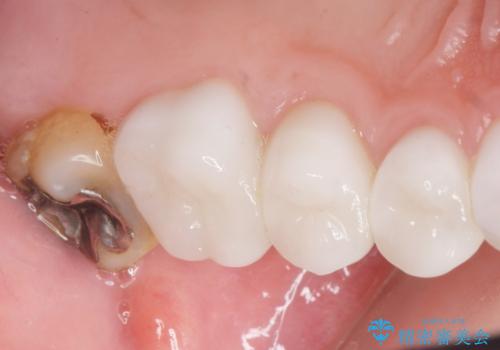

- K-POP(Kポップ)アイドルのような歯にしたいと希望され来院された患者様です。

矯正を途中でやめてしまったとのことで、歯に矯正の接着材が残っており着色も顕著でした。

奥歯の咬合面にはレジンが盛られた状態でした。

見た目と咬み合わせを改善するため、セラミッククラウンによる治療を行いました。